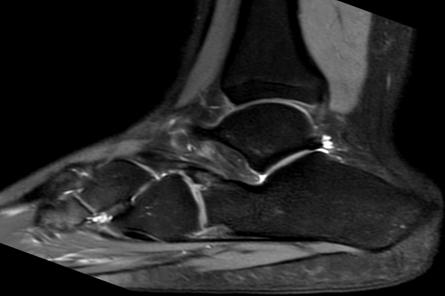

A 15-year-old female was consulted at our outpatient clinic with a two-year history of multiple right ankle sprains and persisting load-dependent disturbance. She had never presented with local ecchymosis suggestive of a fracture. Radiological evaluation (X-ray and MRI) suggested an OCS but also revealed a synchondrosis/synfibrosis between the tip of the anterior calcaneal process and the navicular bone (Figures 2a-b). On palpation, there was elective pain on the anterolateral side of the mid foot, and she had restricted subtalar motion. Clinicians proposed a surgical exploration using a lateral approach, revealing synchondrosis/synfibrosis between the calcaneal body and the anterior calcaneal process and between an OCS and the navicular bone. A surgical excision of the OCS was performed, and the extensor digitorum brevis muscle was interposed in the gap left by the removal of the bony piece. The treatment quickly and fully resolved the pain and improved subtalar motion, and three months after surgery, the patient resumed her physical activities painlessly.

Figures 2a-b: A sagittal MRI of the right foot suggestive of an OCS but also revealing a synchondrosis/synfibrosis between the tip of the anterior calcaneal process and the navicular bone. Figures 3a-b: An MRI scan image showing synchondrosis between the OCS and the calcaneus, confirming the calcaneonavicular coalition.